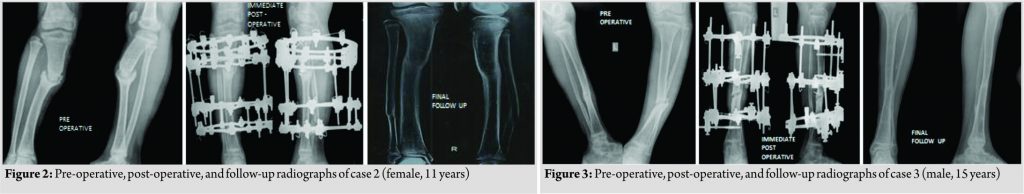

We had four children (3 males and 1 female, age 4–15 years) with hypertrophic nonunion of the tibia. Three of them were post-traumatic. The fourth patient had tibial bone defect following acute osteomyelitis. He underwent tibialisation of the fibula elsewhere. The distal junction united uneventfully, but the proximal junction went in for hypertrophic nonunion. The demographic and clinical characteristics of our patient cohort are summarized in Table 1 (Fig. 1, 2, 3, 4).

The fixators were removed after satisfactory stress test after loosening all connecting rods. Patellar tendon bearing cast was given for all cases for 6 weeks with the advice of full weight-bearing. Apart from limb swelling and blebs in one case, another patient had pin tract infection that was detected at first follow-up that needed a week of dressings and oral antibiotics. The infection settled uneventfully without any need of wire exchange. Two patients each had minimal residual deformity and shortening <1 cm, well within acceptable limits with potential to remodel. The intraoperative, post-operative, and follow-up characteristics of our patient cohort are summarized in Table 2 (Fig. 1, 2, 3, 4).